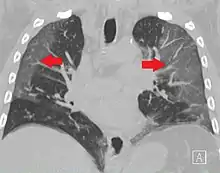

La revista The Lancet publicó el 24 de enero de 2020 un estudio de los primeros 41 casos de pacientes ingresados (en hospital de Wuhan) con el diagnóstico confirmado, desde el 16 de diciembre de 2019 al 2 de enero de 2020.[105] De ellos, menos de la mitad tenían enfermedades subyacentes, entre ellas diabetes, hipertensión y enfermedad cardiovascular. Los síntomas comunes al inicio de la enfermedad fueron fiebre, tos seca y mialgias o fatiga; los síntomas menos comunes fueron la producción de esputo, cefalea, hemoptisis y diarrea. La disnea se desarrolló en 22 de 40 pacientes (55 %), con una mediana del tiempo desde el inicio de la enfermedad hasta la disnea de ocho días. Presentaron linfopenia 26 de 41 pacientes (63 %). Todos los pacientes tuvieron neumonía con hallazgos anormales en la TC de tórax.[115]

La radiología torácica (bien por radiografía, tomografía computerizada o ecografía) puede ayudar al diagnóstico de COVID-19 e identificar o descartar complicaciones pulmonares.[171]